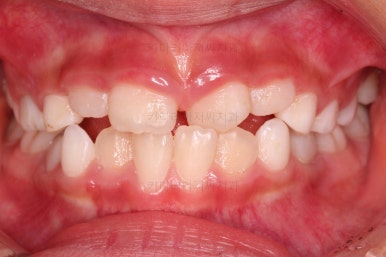

부산어린이반대교합 초진 시, 치열의 모습이에요.

우선 유치들이 많이 썩어서 치료가 필요해 보였고요.

앞니가 거꾸로 물려있고(아래 앞니가 위 앞니보다 앞으로 튀어나간 상황) 삐뚤어 있어요.